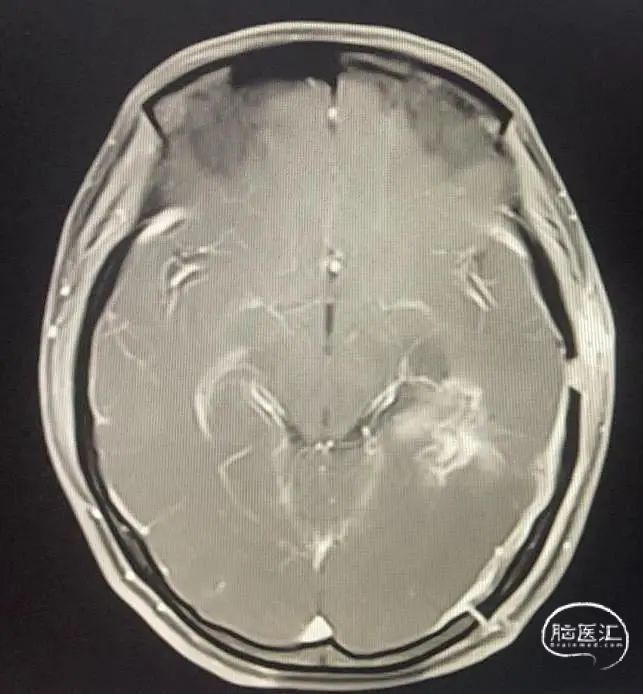

术后复查情况

图3

图4